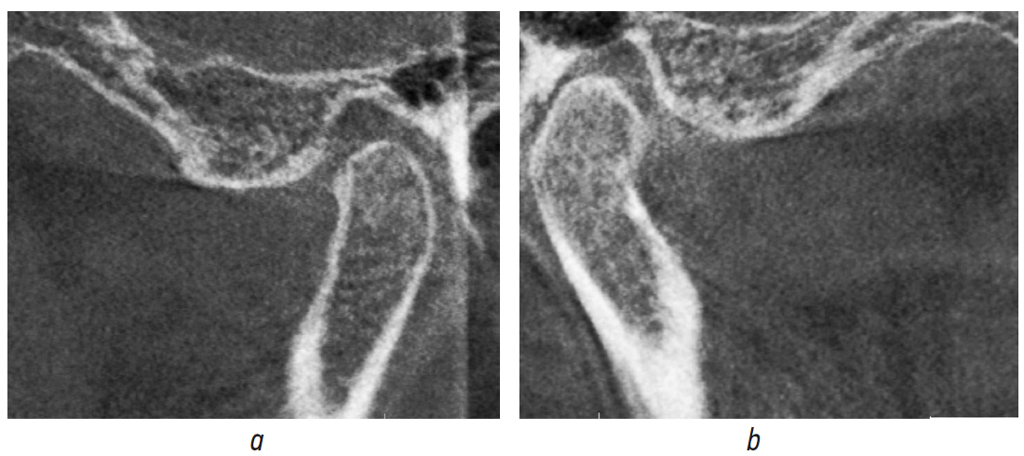

Computed tomography (CT) of the mandibles (Fig. 1), CT of the TMJ (Fig. 2), electromyography of the mandibular muscles (Fig. 3), and sonography of the TMJ (Fig. 4) were performed for diagnostic purposes.

Fig. 2. Pretreatment computed tomography of the right (a) and left (b) temporomandibular joint

Рис. 2. Компьютерная томограмма правого (a) и левого (b) височно-нижнечелюстного сустава до лечения

The CT of the TMJ revealed that the head of the mandible was displaced distally on the right side. The mandibular heads were deformed on both sides. Electromyography revealed increased tone of temporal and bicuspid muscles at the existing position of the mandible. Sonography revealed the presence of clicks on the right and left TMJ regions when opening and closing of the mouth. The preliminary diagnosis was confirmed based on the diagnostic measures.